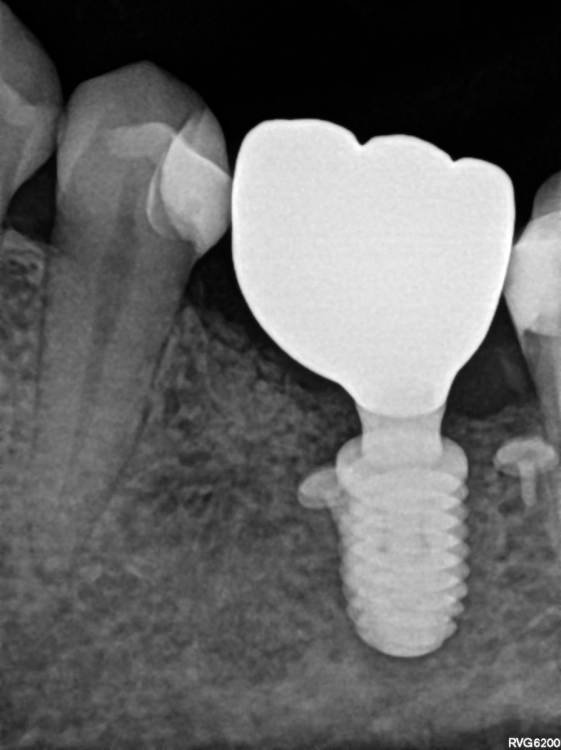

TIGER Опубликовано 14 июля, 2023 Автор Поделиться Опубликовано 14 июля, 2023 всем привет!Не всегда одномоментная имплантация метод выбора,в данном кейсе пошёл по более прогнозируемому пути для сохранения тканей 1 1 Ссылка на комментарий

TIGER Опубликовано 14 июля, 2023 Автор Поделиться Опубликовано 14 июля, 2023 @Fin 2 й этап имплант&нкр Ссылка на комментарий

Irouil Опубликовано 15 июля, 2023 Поделиться Опубликовано 15 июля, 2023 Интересно, одномоментно в лунку дистального корня не зашло бы? Предположу, что либо ангуляция вышла бы экстремальной, либо слишком близко к вестибулярной стенке пришлось бы ставить Вообще, эти случаи с выраженным поднутрением в боковых отделах нижней челюсти достаточно коварные, на мой взгляд, с точки зрения позиционирования 1 Ссылка на комментарий

TIGER Опубликовано 15 июля, 2023 Автор Поделиться Опубликовано 15 июля, 2023 @Irouil было бы сложно стабилизировать в этих условиях,в случае неуда ситуация усугблялась,решил пойти по пути сохранения тканей,дал организму самому регенирировать,при имплантации добавил чуть тканей @Doc ещё Миш писал в книге о минусах имплантации семёрок кстати 1 Ссылка на комментарий